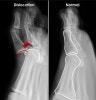

X-ray : 발가락 관절의 탈구(MTPJ Dislocation)

X-ray 촬영을 실시합니다.